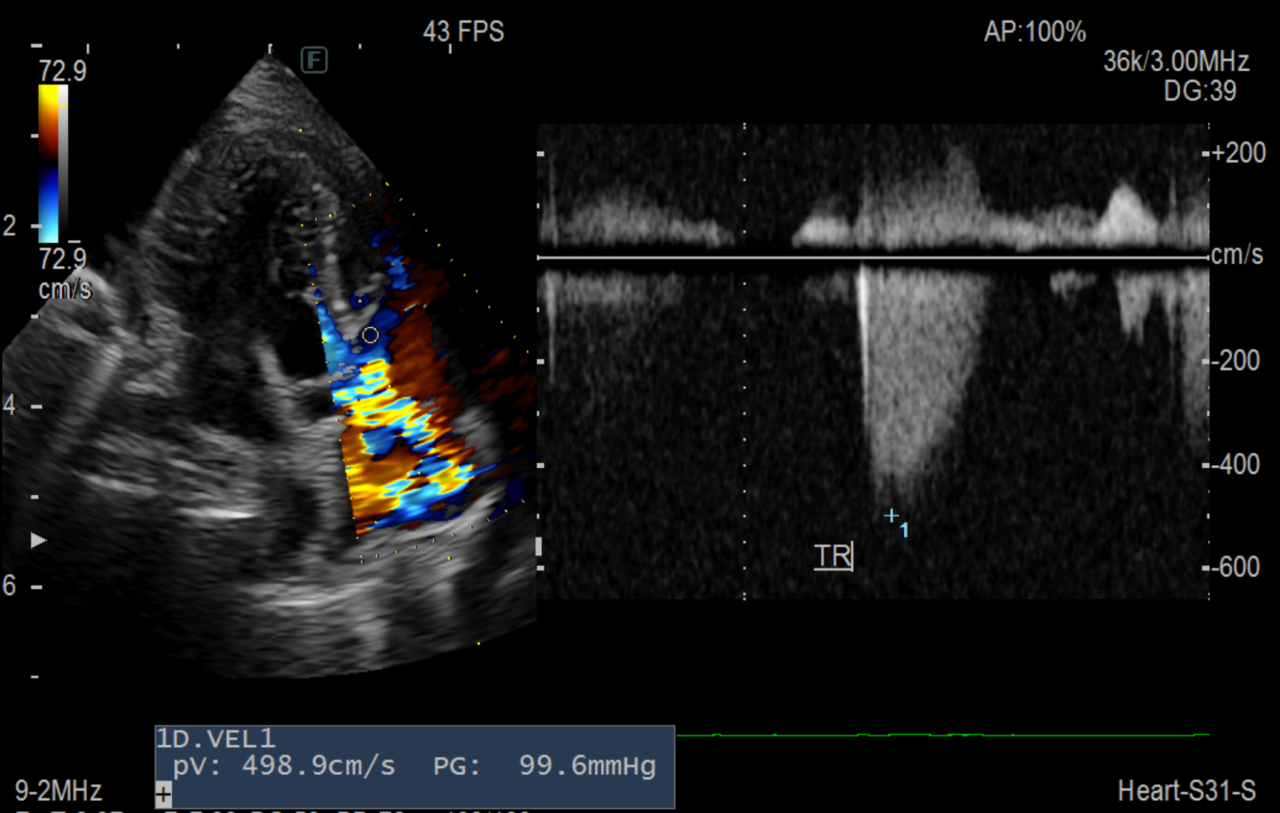

心機能検査を行うと、右心の三尖弁閉鎖不全が重度であり肺高血圧症が示唆されました。

この患者さんは利尿薬と肺血管拡張薬により症状は改善し、3ヶ月内服治療を行なっていますが再発はなく安定しています。